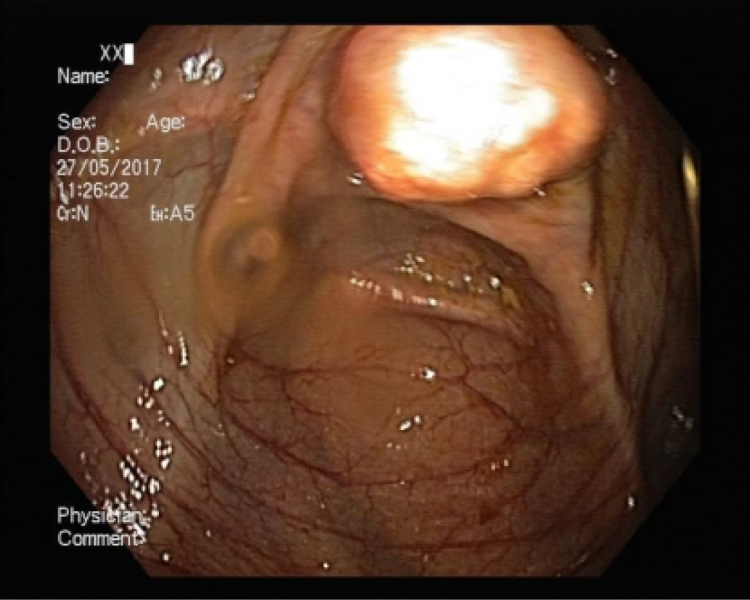

An unusual cause of upper gastrointestinal bleeding and small bowel obstruction

An unusual cause of upper gastrointestinal bleeding and small bowel obstruction

Maria Pia Costa Santos, Alexandre Ferreira, Vera Silveira, Luísa Glória, Marília Cravo

A 58-year-old black female, born in Angola, presented with melena, vomiting and a 7-year history of a right thigh mass that progressively increased in size. Her laboratory tests revealed iron deficiency anemia (hemoglobin 4.4g/dL). Computed tomography showed a large solid lesion in the right thigh, multiple smaller lesions in the lungs, pancreas and uterus, focal thickness of the small bowel wall and jejunal intussusception. Upper gastrointestinal endoscopy revealed multiple ulcerative lesions with elevated edges throughout the second and third portions of the duodenum, with 10-20 millimeters, without hemorrhagic stigmata. The histology of the duodenal and thigh lesions revealed a leiomyosarcoma.

An unusual cause of upper gastrointestinal bleeding and small bowel obstruction